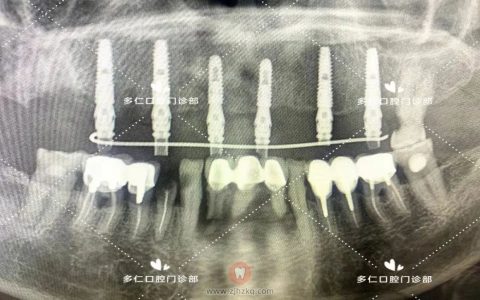

术后全景片